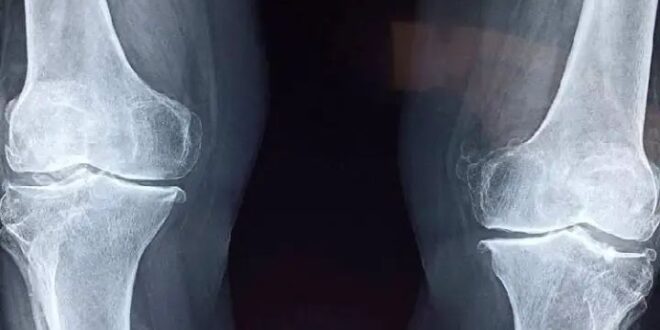

ದಕ್ಷಿಣ ಕೊರಿಯಾದ ಸಾಂಗ್ಕ್ಯುಂಕ್ವಾನ್ ವಿಶ್ವವಿದ್ಯಾಲಯದ ಸಂಶೋಧಕರು ಮೂಳೆಯಲ್ಲಿ ಹೊಸ ಆವಿಷ್ಕಾರವನ್ನು ಮಾಡಿದ್ದಾರೆ. ಅವರು ಸಾಮಾನ್ಯ ಅಂಟು ಗನ್ ಅನ್ನು 3D ಮುದ್ರಣ ಯಂತ್ರದೊಂದಿಗೆ ಬದಲಾಯಿಸಿದ್ದಾರೆ, ಅದು ಮೂಳೆಯಂತಹ ವಸ್ತುಗಳನ್ನು ನೇರವಾಗಿ ಮುರಿದ ಮೂಳೆಗಳ ಮೇಲೆ ಮುದ್ರಿಸಬಹುದು.ಹೊಸ ತಂತ್ರಜ್ಞಾನವು ಸಂಕೀರ್ಣ ಮೂಳೆ ಶಸ್ತ್ರಚಿಕಿತ್ಸೆಯನ್ನು ಸುಲಭ ಮತ್ತು ಪರಿಣಾಮಕಾರಿಯಾಗಿ ಮಾಡಬಹುದು ಎಂದು ಅಧ್ಯಯನವನ್ನು ನಡೆಸಿದ ವಿಜ್ಞಾನಿಗಳು ಹೇಳುತ್ತಾರೆ.ಹೊಸ ತಂತ್ರಜ್ಞಾನವನ್ನು ಕಂಡುಹಿಡಿದ ಜಂಗ್ ಸೆಯುಂಗ್ ಲೀ ಮಾತನಾಡಿ, ನಮ್ಮ ತಂತ್ರಜ್ಞಾನವು ಶಸ್ತ್ರಚಿಕಿತ್ಸೆಯ ಸಮಯದಲ್ಲಿ ಮುರಿದ ಮೂಳೆಯ ಮೇಲೆ ನೇರವಾಗಿ ಸ್ಕ್ಯಾಫೋಲ್ಡ್ (ಮೂಳೆ ತರಹದ ರಚನೆ) ಅನ್ನು ರಚಿಸುವ ಮತ್ತು ಅನ್ವಯಿಸುವ ವಿಶೇಷ ವ್ಯವಸ್ಥೆಯಾಗಿದೆ